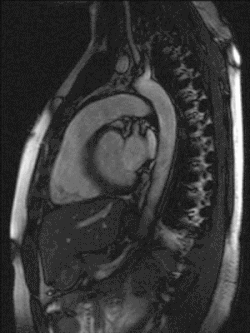

Drogas vasoativas se refere às substâncias que apresentam efeitos vasculares periféricos, pulmonares ou cardíacos, sejam eles diretos ou indiretos, atuando em pequenas doses e com respostas dose dependente de efeito rápido e curto, através de receptores situados no endotélio vascular. São de uso corriqueiro em uma unidade de terapia intensiva (UTI) principalmente para regular a frequência cardíaca e volume sistólico. [1]